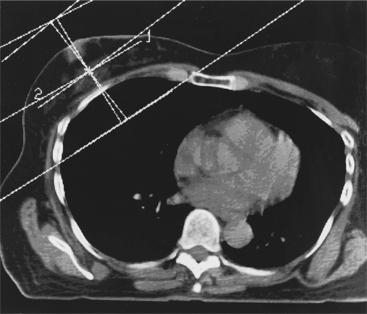

Most women receive radiation therapy after a lumpectomy to eradicate any cancer cells that may remain in the affected breast or nearby lymph nodes. Usually, radiation is delivered to the whole breast once a day, 5 days a week, for about 6 weeks (Fig. 20-19).

Figure 20-19 The standard radiation field configuration for breast cancer. Two tangentially directed fields encompass the breast with a minimal amount of underlying lung tissue. The contralateral breast and all of the critical structures are avoided. (From Abeloff MD: Clinical oncology, ed 3, Philadelphia, 2004, Churchill Livingstone.)

Software algorithms used to produce discriminating radiation fields conform the radiation to the breast, chest wall, and/or regional lymph nodes to achieve a homog- enous dose to the breast and decrease or avoid doses to the ribs, lung, and heart. This technology has allowed greater adaptation to a variety of breast and chest wall shapes.35